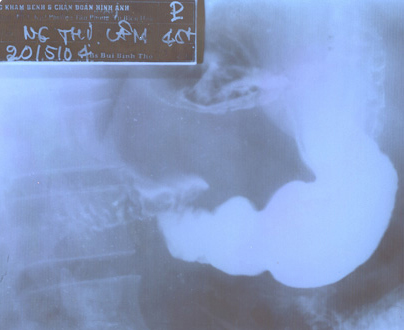

Image TOGD mono contrast

baryte un ulcere bulbaire sclerosante avec image de

niche arondie au milieure de la bulbe |

Ulcere bulbaire sclerosant

avec deformation en etoile du bulbe . Technique TOGD

a double de contrast |